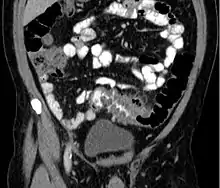

Diverticulitis on a CT scan in a coronal view

People with the above symptoms are commonly studied with computed tomography, or a CT scan.[29] Ultrasound can provide preliminary investigation for diverticulitis. Amongst the findings that can be seen on ultrasound is non-compressing outpouching of bowel wall, hypoechoic and thickened wall, or there is obstructive fecalith at the bowel wall. Besides, bowel wall oedema with adjacent hyperechoic mesentery can also be seen on ultrasound. However, CT scan is the mainstay of diagnosing diverticulitis and its complications.[14] The diagnosis of acute diverticulitis is made confidently when the involved segment contains diverticula.[30] CT images reveal localized colon wall thickening, with inflammation extending into the fat surrounding the colon.[31] Amongst the complications that can be seen on CT scan are: abscesses, perforation, pylephlebitis, intestinal obstruction, bleeding, and fistula.[14]